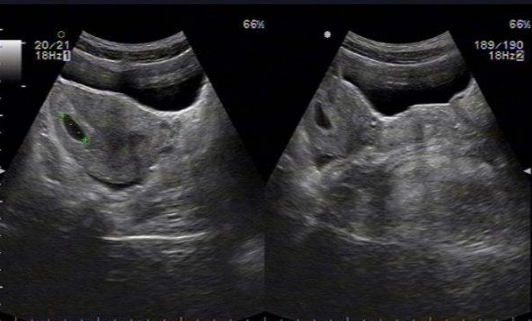

雙角子宮圖片

A:雙角子宮的人並不多,因為這屬於子宮異常的一種,一般在平時並不會有任何的不適症狀,往往是在發生自然流產的時候,做B超檢查出來有子宮畸形。雙角子宮宮腔形態發生改變,往往會影響到受精卵著床,另外也會妨礙受精卵繼續增大,所以容易刺激出現子宮收縮,出……

A:雙角子宮是一種子宮發育畸形的狀態,主要是患者子宮底部融合不完全導致的,患者進行B超或者是宮腔鏡檢查能夠發現子宮和正常女性相比不規則。嚴重的雙角子宮患者也有可能會伴有明顯的腹痛,或者來月經期間有痛經症狀。患者在懷孕時容易造成胎位不正,胎兒不能……

A:雙角子宮根據宮角在宮底水平融合不全的程度,分為完全性的雙角子宮和不全性雙角子宮。一般情況下,雙角子宮是沒有臨床症狀,所以不易發現。有時候雙角子宮會合併有月經量多或者是不同程度的痛經。行婦科檢查的時候可以觸及宮底部是有凹陷的,一般都是通過超聲……